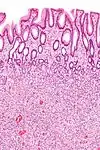

| Fundic gland polyp | Fundus of stomach | Cystically dilated glands lined by chief cells, parietal cells and mucinous foveolar cells.[5] | Very low or none, when sporadic.[6] | ![]() |

Fundic gland polyposis |